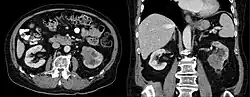

Das Ductus-Bellini-Karzinom ist eine sehr seltene Form eines Nierenzellkarzinoms, die von den Sammelrohren (lateinisch Tubulus renalis colligens, Ductus Bellini) ausgeht.[1][2][3]

Das klinische Erscheinungsbild und die Diagnostik entspricht dem unter Nierenzellkarzinom Beschriebenem. Diese Tumorform gilt als besonders aggressiv.[1][2]